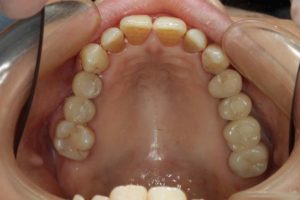

- 術前

- 術後

- インプラント手術直後のレントゲン

長い間お疲れさまでした。この方は、前歯に審美的なインプラントを入れるため、抜歯後4ヶ月待ち、仮歯で歯肉が成熟するのを数が月待っていたりした為に、完成まで時間がかかってしまいました。

虫歯治療などは短期間で終えることができるのですが、歯ぐきをいじり出すとどうしても治癒期間が必要となり長くなってしまいます。それもこれも奇麗な仕上がりのために欠くことのできないものです。何卒ご容赦を!